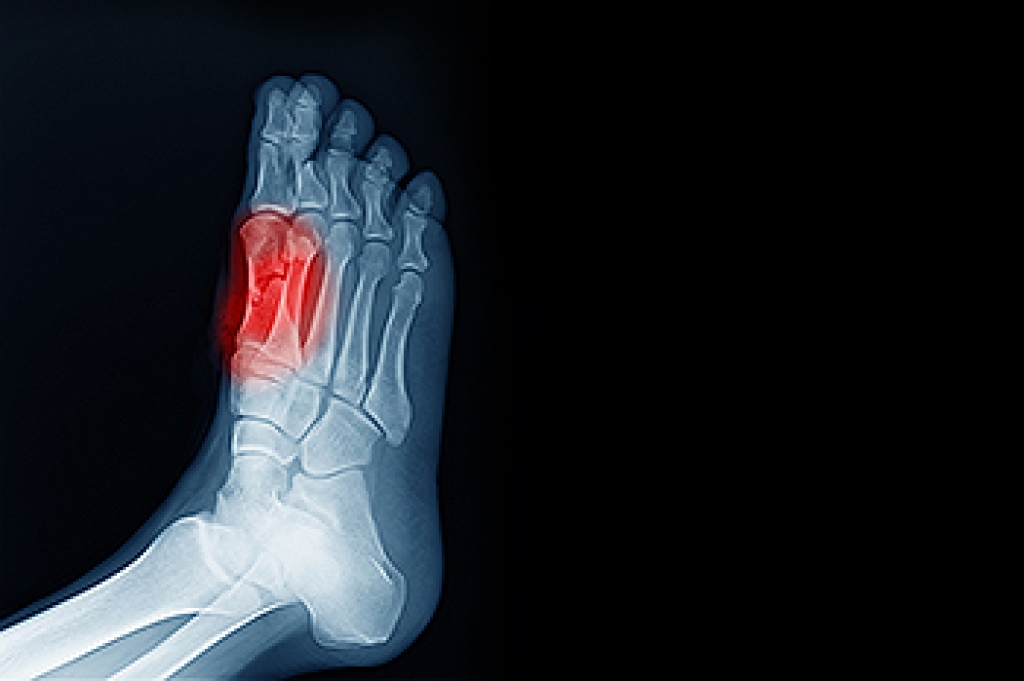

Sesamoiditis is a painful condition involving irritation and inflammation of the tendons surrounding the sesamoid bones. These are small bones located beneath the big toe joint that help absorb weight and assist with movement when walking and running. The condition develops from repetitive stress, overuse, or excessive pressure on the ball of the foot. Symptoms often include aching pain beneath the big toe, swelling, bruising, and discomfort that worsens with activity. Activities that place repeated strain on the forefoot, such as ballet dancing and sports, are more likely to cause this condition. A podiatrist can provide an accurate diagnosis, offloading strategies, and customized treatment. If you have pain in this part of your foot, it is suggested that you consult a podiatrist who can accurately diagnose and treat what may be going on.

Sesamoiditis is a condition of the foot that affects the ball of the foot. It is more common in younger people than it is in older people. It can also occur with people who have begun a new exercise program, since their bodies are adjusting to the new physical regimen. Pain may also be caused by the inflammation of tendons surrounding the bones. It is important to seek treatment in its early stages because if you ignore the pain, this condition can lead to more serious problems such as severe irritation and bone fractures.